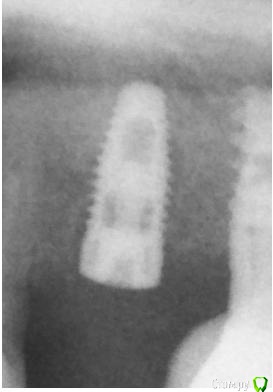

Jurai Опубликовано 7 мая, 2015 Поделиться Опубликовано 7 мая, 2015 25, Нобель, одномоментно, 3 месяца назад. Переставить или "и так сойдет™"? Не раскрывала еще, снимка после установки нет в доступе, придется верить на слово - дистально был в кости, заглублен нормально. Ссылка на комментарий

Jurai Опубликовано 7 мая, 2015 Автор Поделиться Опубликовано 7 мая, 2015 то, что микрорезьба открыта, пусть и частично пока, пару лет пройдет -будет из десны торчать Ссылка на комментарий

Maxfac Опубликовано 7 мая, 2015 Поделиться Опубликовано 7 мая, 2015 Добавлю. И какой прогноз для такого имплантата? Пациентка настаивает на переделке, все сейчас грамотные, спасибо интернету.Вообще, особого криминала на рентгене не видно - прогноз благоприятный. Надо бы еще фото для полной картины. Ссылка на комментарий